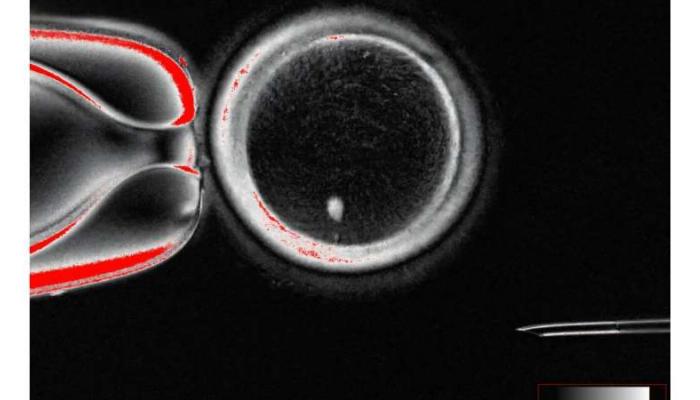

في إنجاز وُصف بالاختراق العلمي، أعلن باحثون من جامعة أوريغون الأمريكية عن نجاحهم في إنتاج بويضات بشرية من خلايا الجلد.